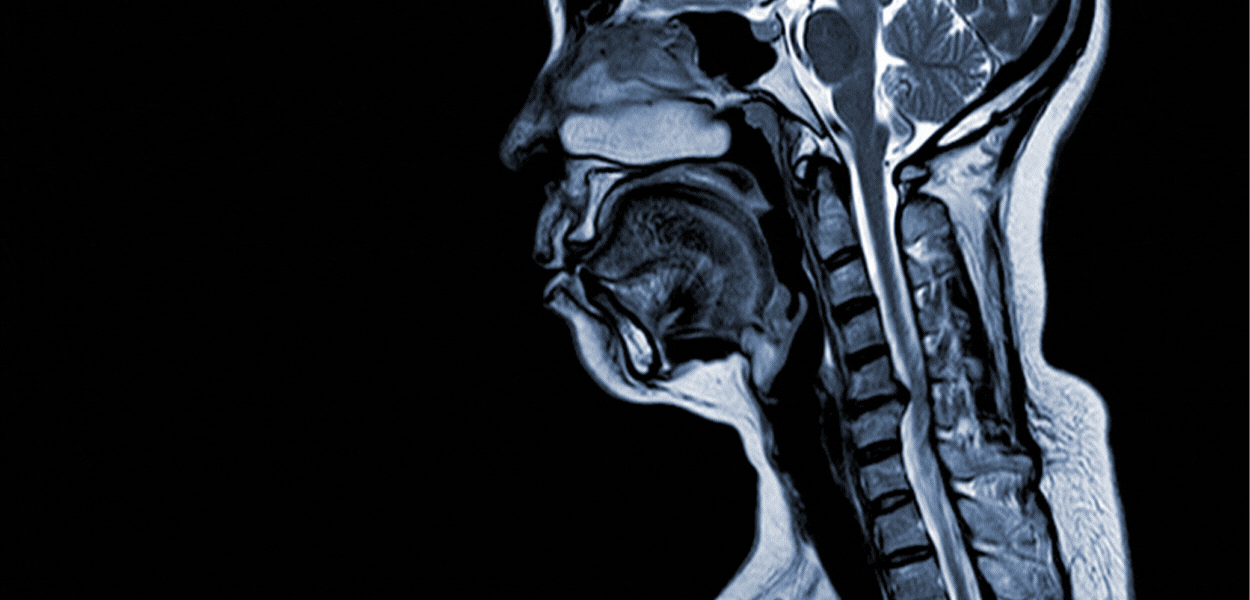

La Resonancia Magnética, también conocida por la sigla RM es una técnica de imagenología por imagen cuyo funcionamiento se basa en enviar ondas de radio frecuencia que interaccionan con los átomos de hidrógeno del cuerpo mientras están sometidos a un potente campo magnético que rodea al paciente. La RM permite obtener imágenes de gran precisión de distintas partes del cuerpo. Esta técnica imagenológica requiere en algunos casos la administración de medio de contraste paramagnético, para aumentar la sensibilidad diagnóstica.

• Resonancia de cráneo-cerebro